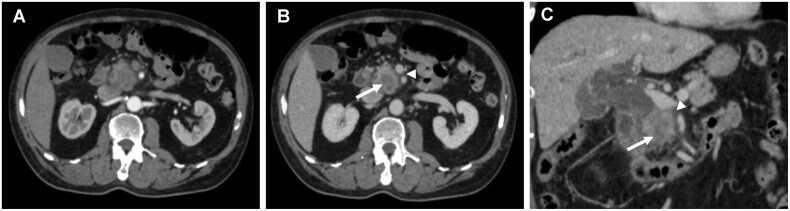

A total of 149 patients were evaluated (median age: 67 years; interquartile range: 41-89 years; 82 men), among whom 70 (47.0 %) experienced early recurrence. Rim enhancement, tumor necrosis, peripancreatic tumor infiltration, and suspicious metastatic lymph nodes, were independently associated with early recurrence. When any two or more of these four significant imaging features were combined, the specificity was 86.1 % (68/79) and the sensitivity was 88.6 % (60/70). DFS and OS were significantly worse in PDAC patients with two or more of these features compared to those with none or only one (all log-rank  < 0.001).

A combination of two or more imaging features such as rim enhancement, tumor necrosis, peripancreatic tumor infiltration, and suspicious metastatic lymph nodes, could be used as a prognostic imaging marker for early recurrence, demonstrating effective diagnostic performance and an association with DFS and OS after pancreatoduodenectomy of PDAC.